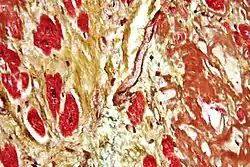

Healthy myocardium versus interstitial fibrosis in dilated cardiomyopathy. Alcian blue stain.

Healthy myocardium versus interstitial fibrosis in dilated cardiomyopathy. Alcian blue stain. -